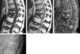

Traumatic vertebral osteonecrosis